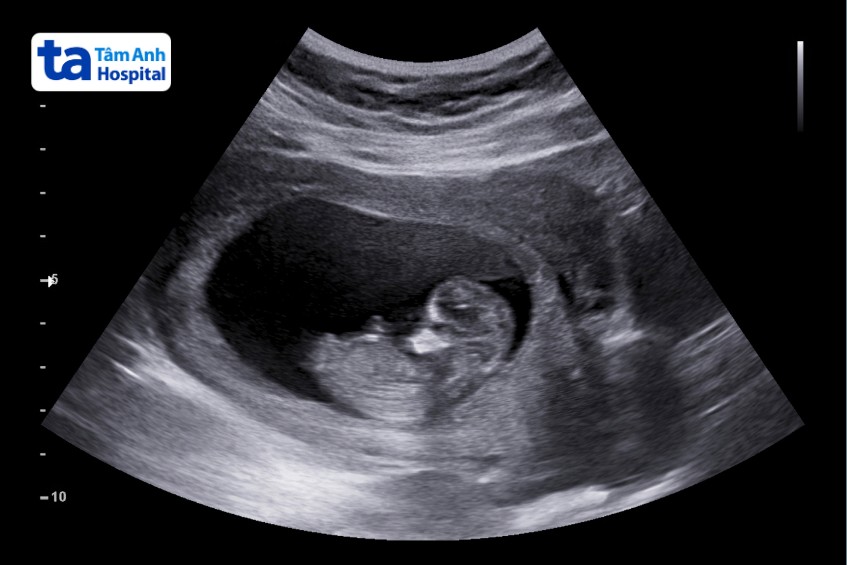

Thông thường, siêu âm 2D được sử dụng trong siêu âm tổng quát sản phụ khoa. Máy có khả năng tạo hình ảnh 2 chiều của những gì bên trong cơ thể. Máy sử dụng công nghệ 2D, cho phép cung cấp các hình ảnh về kích thước, cấu trúc các cơ quan trong cơ thể, tim thai và sự phát triển của thai nhi, tính toán tuổi thai, dự sinh…

Máy siêu âm được sử dụng để xác định có thai, theo dõi các giai đoạn khác nhau của thai kỳ. Giúp xác định kích thước, sự phát triển của thai nhi cũng như ngày dự sinh. Cung cấp hình ảnh mô tả số lượng và giới tính thai nhi. Giúp phát hiện các bất thường về thai nhi như vị trí thai ngoài tử cung, bất thường dị tật thai nhi…